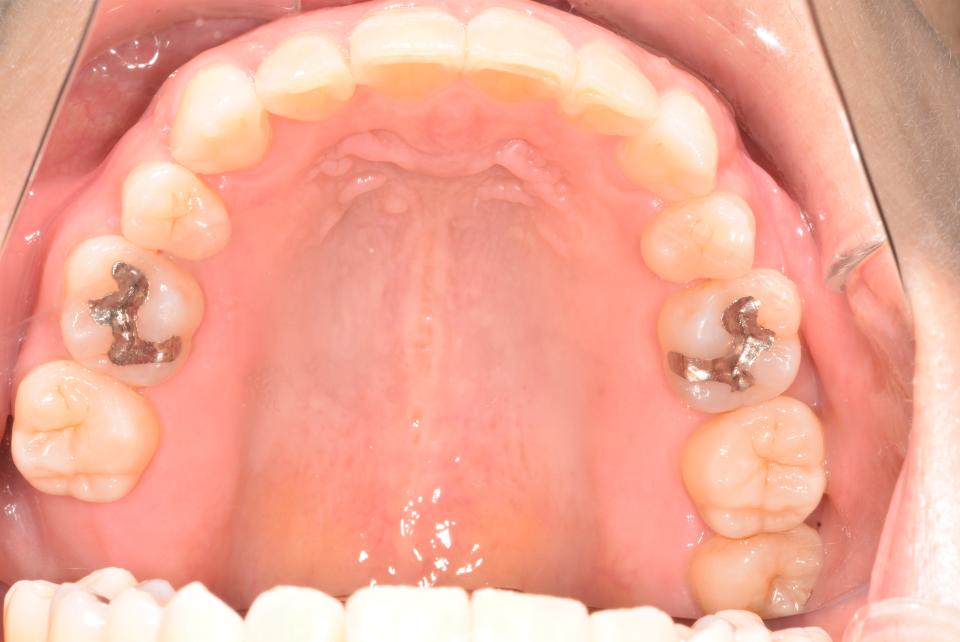

八重歯のマウスピース型矯正治療例(抜歯あり)

矯正治療前

40代女性の患者さんです。

八重歯が気になり矯正治療を始めました。

上の左右4番目の抜歯をして、マウスピース型の矯正治療装置を使用し、歯のやすり掛け(IPR)を行いました。